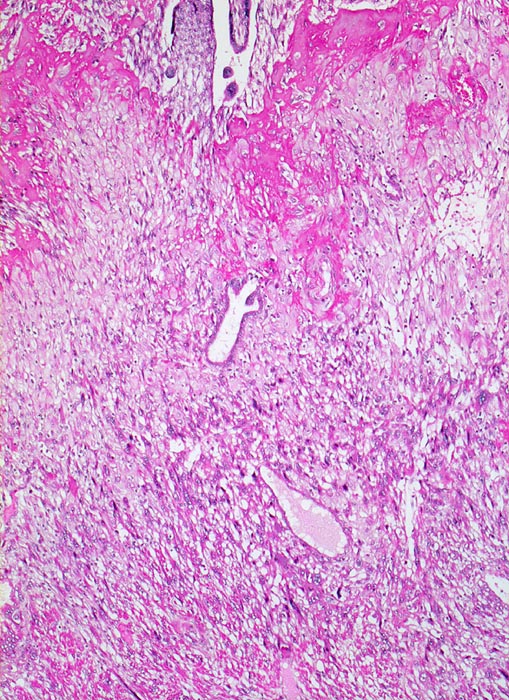

Morphologie:

• Plazenta accreta: Plazentarzotten haften dem Myometrium an ohne deziduale Zwischenschicht. Fibrin und Trophoblast kann vorhanden sein.

• Plazenta increta: Plazentaimplantation innerhalb des Myometriums.

• Plazenta percreta: Penetration der Plazentarzotten durch die gesamte Dicke des Myometriums hindurch.